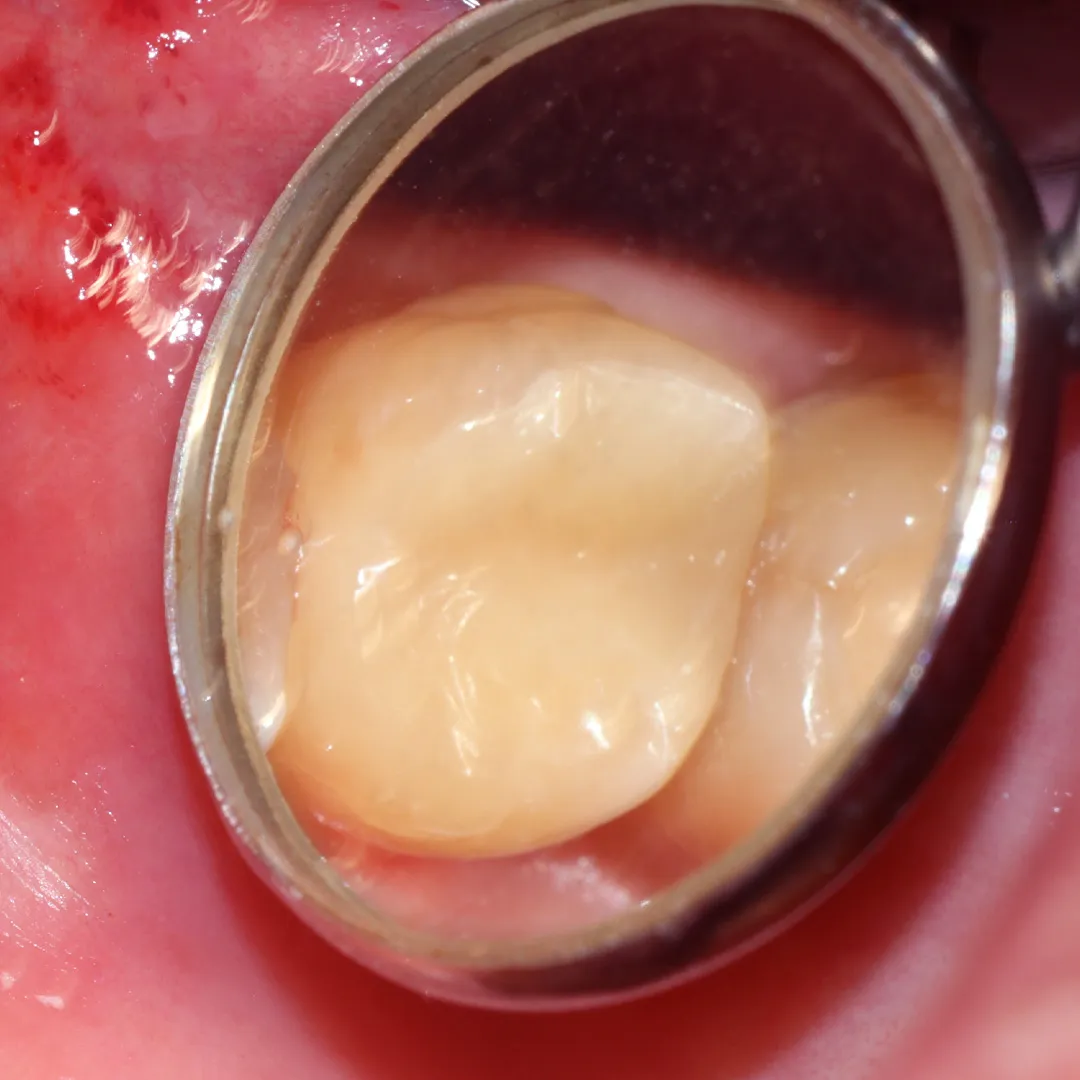

Результаты лечения глубокого кариеса на фото до и послеСмотреть работуСрок лечения:1 визитСумма лечения:6 820 р.